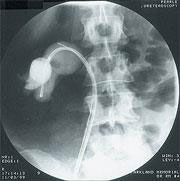

Mnogo češće se bubrežno kamenje pronađe na rentgenskim snimcima ili ultrazvučnom pregledu osoba koje se žale na pojavu krvi u urinu ili na iznenadan bol. Ove dijagnostičke procedure daju lekaru dragocene informacije o veličini kamena i njegovoj lokaciji. Analize krvi i urina pomažu da se otkrije bilo koje stanje koje može podstaći formiranje kamena.

Lekar može odlučiti da snimi urinarni trakt posebnim rentgenskim pregledom koji se zove IVP (intravenska pijelografija). Rezultati ovog snimanja pomažu u određivanju pravilnog lečenja.